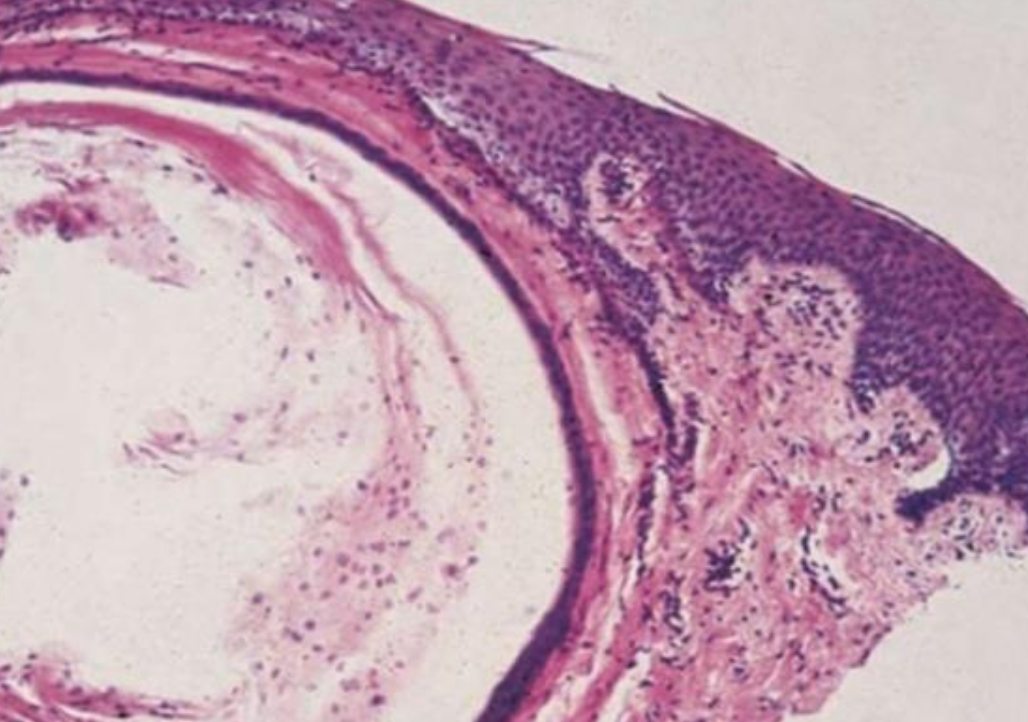

| Periapical(radicular) cysts | Rest of Malassez 被刺激 | - | - | true/ periapical cyst 圓形的光通性包圍根尖 |

牙根吸收, 2cm ↑ 根管治療無效  |

- Rest of Malassez

- Hertwig’s epithelial 殘留

- Rushton bodies

- 齒源系上皮